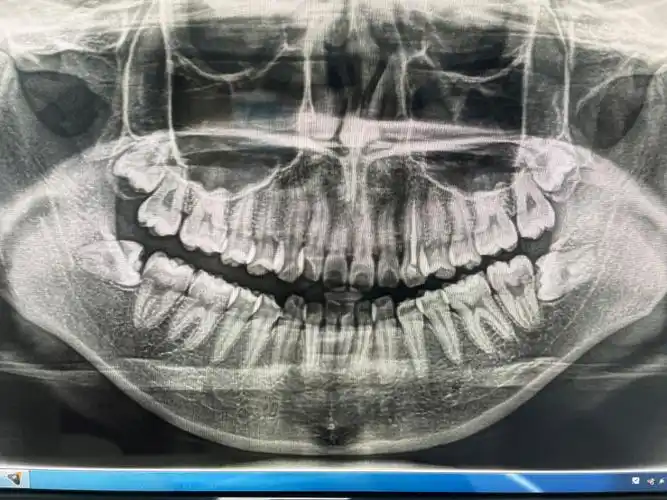

一次拔两颗智齿后悔死了,有人拔牙之后得了干槽症痛不欲生-热点-奇诺

拔智齿注意事项与禁忌,过来人经验(附智齿拔牙后窟窿恢复图)

阻生智齿拔牙

某医上颌智齿拔除实拍一颗牙的陨落的瞬间